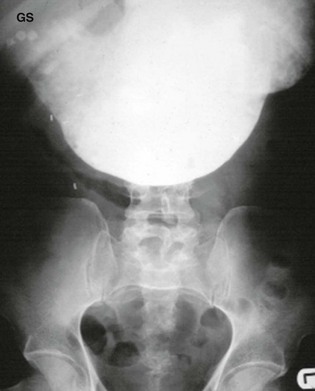

On clinical examination, undernourishment, dehydration, constipation, weakness and weight loss may dominate the picture. Because the stomach is full of residual fluid and food, shaking the patient's abdomen from side to side produces an audible succussion splash. Gastric peristalsis may be visible in longstanding cases and a dilated stomach full of residual food may be palpable. On plain abdominal X-ray, it may be possible to see the grossly dilated stomach filled with mottled food material.

Several gastric washouts using a large-bore oral tube may be necessary to clear the gastric residue before endoscopy or barium meal is attempted.